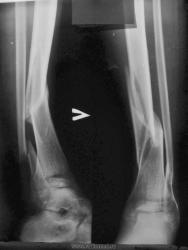

1. Пациент пришел на R-контроль сращения. Два месяца лечения в гипсе. Выяснилось, что в процессе лечения дома снимал лонгет, а на прием к врачу одевал.

Ваше мнение о наличии консолидации?

1. Консолидации конечно, такой как должно, нет. Вопрос1- почему не оперирован? Вопрос2-для себя, это последствия ДТП (ведь имееется "бампер-перелом")?